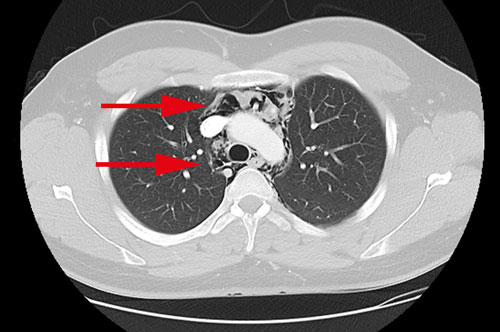

En översiktlig ultraljudsundersökning av hjärtat gjordes bedside för att se eventuell perikardvätska. Patientens hjärta var svårundersökt med ultraljud och kunde inte visualiseras i sin helhet, vilket är ovanligt hos en yngre normalbyggd man. Någon tydlig perikardvätska kunde dock inte påvisas. Blodprov visade normala värden för troponin T, CRP och LPK. För att utesluta pneumotorax gjordes lungröntgen som visade en luftspalt i mediastinum och kring hjärtat, fynd som vid pneumomediastinum och pneumoperikardium (Figur 1). I syfte att utesluta framför allt esofagusruptur som orsak till pneumomediastinum undersöktes patienten med datortomografi av torax med intravenös och peroral kontrast. Även denna undersökning visade luft i mediastinum och perikardiet. Inga tecken till kontrastläckage från esofagus eller andra patologier kunde påvisas (Figur 2–4). Luften kring hjärtat bedömdes förklara svårigheten att undersöka hjärtat med ultraljud. Mot bakgrund av anamnes och radiologiska fynd ställdes diagnosen spontan pneumomedia­stinum och pneumoperikardium. Ingen ytterligare akut utredning bedömdes nödvändig. Han överflyttades till toraxkliniken vid Karolinska universitetssjukhuset för fortsatt observation och smärtlindring. Han förbättrades snabbt och skrevs ut 3 dagar senare, och vid telefonuppföljning efter en månad var patienten helt återställd.

Figur 3. Datortomografi av torax med intravenös kontrast samt peroral kontrast visar strimmor av luft i perikardiet (övre pilen) samt i bakre mediastinum kring aorta och esofagus (nedre pilen).